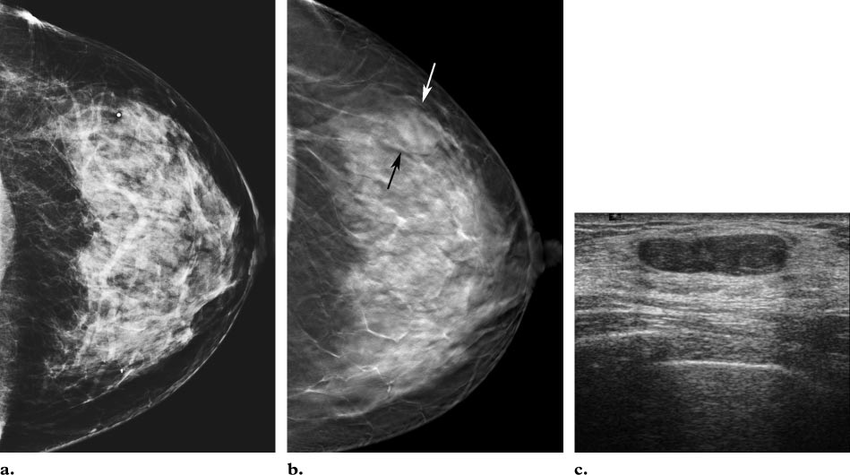

What BIRADS

BIRADS 3

an oval, circumscribed, nonpalpable mass on a baseline mammogram constitutes 1 of the accepted BI-RADS 3 (probably benign) lesions.

What do you expect to find on US?

Clustered microcysts

we see a lobular mass with microlobulated borders, isodense with no fat internally